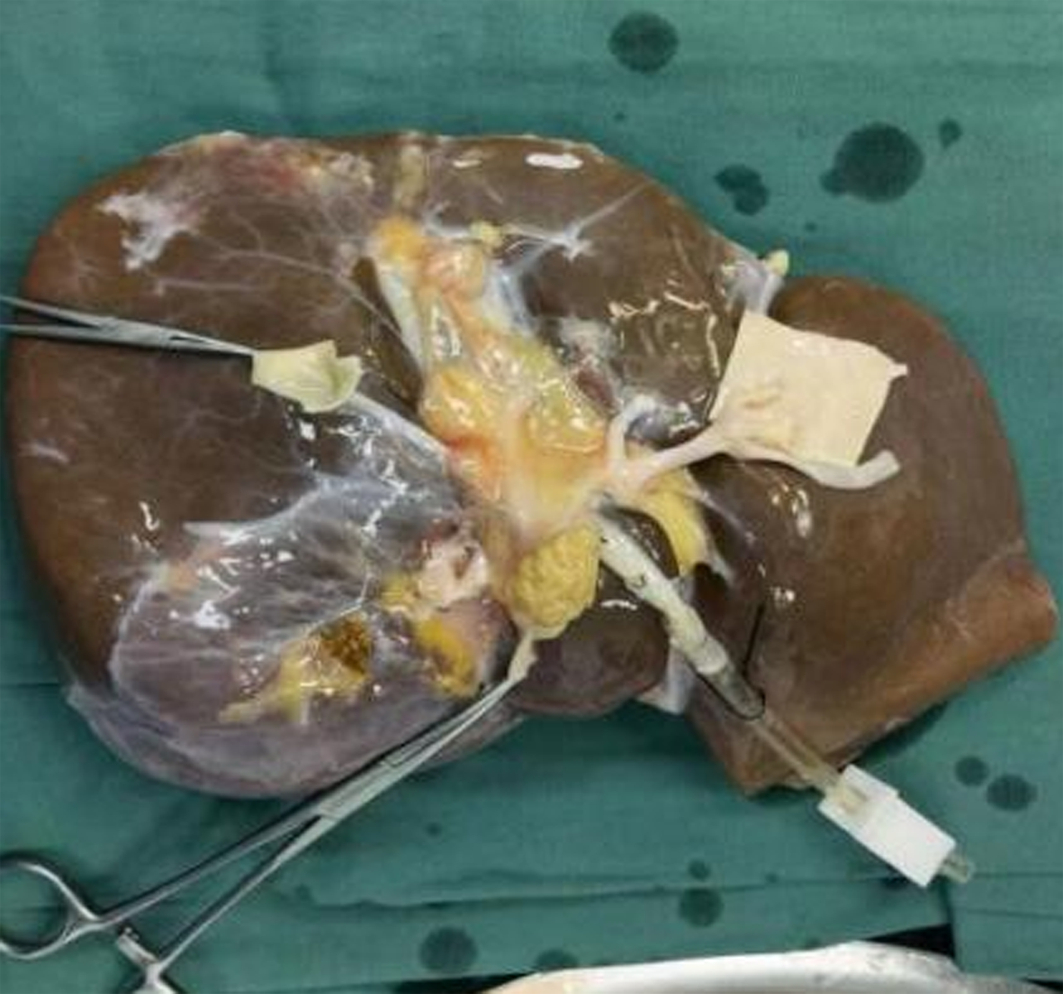

Diagnosis and treatment of hepatic pseudoaneurysm with bile leakage and bile duct hemorrhage after transplantation of donor liver with right hepatic artery variation: A case report

Tian HAN, Rui ZHANG, Zhiyong SHI, Li ZHANG, Jun XU

2022, 38(12): 2818-2820. DOI: 10.3969/j.issn.1001-5256.2022.12.024

Abstract(1727) HTML (1056) PDF (2268KB)(55)